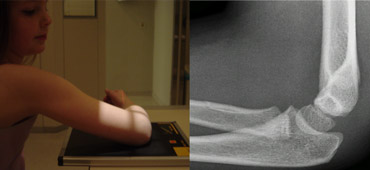

Shoulder higher than elbow. Radius and Capitellum project on to the ulna. Shoulder higher than elbow. Radius and Capitellum project on to the ulna.

Common errors in positioning

Error 1: Shoulder higher than elbow

For a true lateral view the shoulder should be at the level of the elbow.

If the shoulder is higher than the elbow, the radius and capitellum will project on the ulna.

The solution is either to lift the examination table which will lift the elbow or to lower the shoulder by placing the patient on a smaller chair.